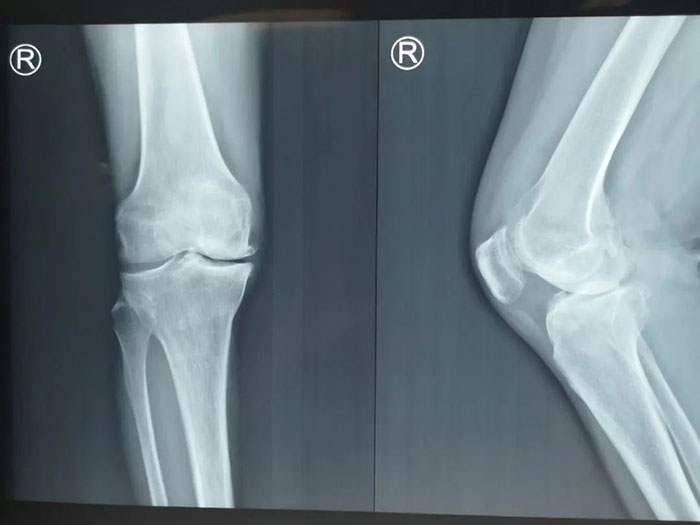

關(guān)節(jié)外二科(骨五科)主任王軍接診查體后發(fā)現(xiàn)其左膝稍腫,內(nèi)側(cè)壓痛,左膝內(nèi)翻呈現(xiàn)出“O”型腿姿態(tài),結(jié)合X光檢查:關(guān)節(jié)間隙非對稱性變窄,軟骨下發(fā)生骨硬化和(或)囊性變,關(guān)節(jié)邊緣有骨贅 ,MRI可見軟骨厚度變薄、缺損,半月板損傷,關(guān)節(jié)積液,骨髓水腫,診斷為左膝關(guān)節(jié)骨性關(guān)節(jié)炎,需進(jìn)行手術(shù)治療。

考慮到患者還年輕,能夠最大限度保留患肢功能,可保障她以后的日常生活。結(jié)合患者實(shí)際情況,關(guān)節(jié)外二科(骨五科)團(tuán)隊(duì)一致認(rèn)為關(guān)節(jié)鏡清理合并脛骨骨高位截骨術(shù)是首選治療方案。